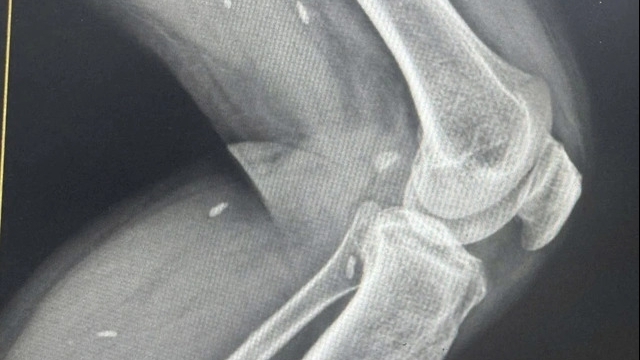

Qua thăm khám, siêu âm, chụp cắt lớp vi tính và làm các xét nghiệm, các bác sỹ phát hiện trong cơ thể bệnh nhân có sỏi niệu quản phải với kích thước gần 5mm nằm sát lỗ niệu quản phải đổ vào bàng quang. Bệnh nhân được chỉ định phẫu thuật nội soi tán sỏi và đặt sonde JJ ngày 17/7/2019.

Tuy nhiên, đến ngày 3/9/2019, bệnh nhân P.H vào viện lần hai tại Khoa Cấp cứu ngoại với số bệnh án BA 30919 với chẩn đoán đái máu/còn sonde JJ, bệnh nhân đã được khám và làm các xét nghiệm; chỉ định phẫu thuật rút sonde ngày 4/9/2019. Sau phẫu thuật, bệnh nhân ổn định sức khỏe và được xuất viện vào ngày 5/9/2019.